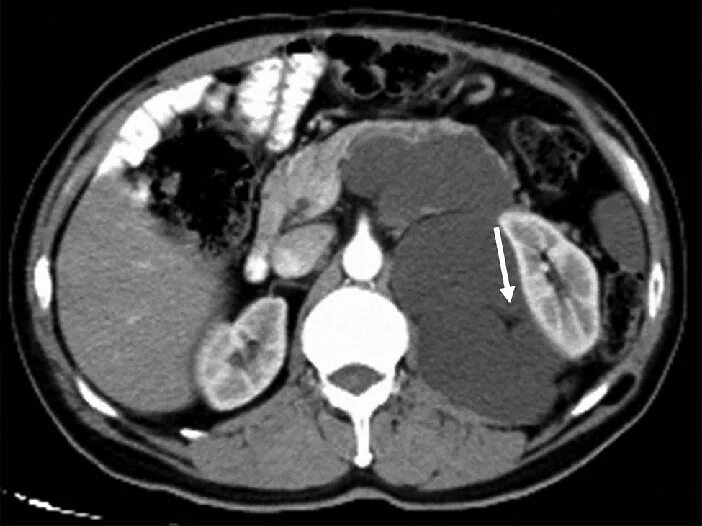

Забрюшинная онкология